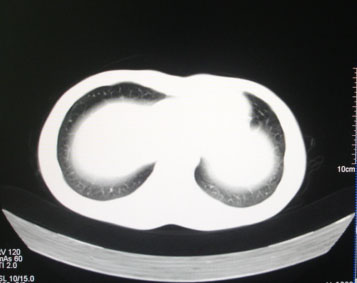

标题: CT26938:单发肺窗

病人17岁。咳嗽伴血丝痰2年?外院x片示左上肺椭圆形影,疑胸腺瘤

左肺尖见占位,建议上传纵隔窗及向上扫描。

左上纵隔占位性病变?